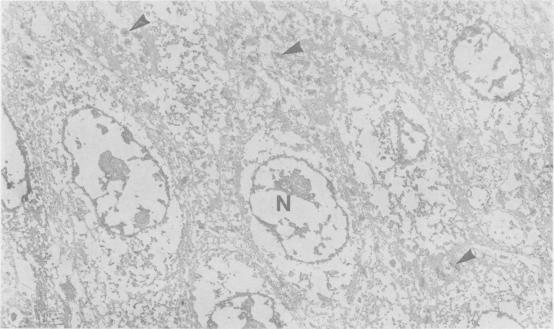

Effects of bile acids and hydrogen ion on the fine structure of oesophageal epithelium.

Oesophageal mucosal biopsies were incubated in 20, 0, and 0.2mM solutions of cholic, chenodeoxycholic, ursodeoxycholic, and deoxycholic bile acids. Both conjugated and unconjugated bile acids were studied at pH 1 and 7 singly and in combination. Observations were also made using 0.1 N hydrochloric acid and human gastric juice at pH 1-3 and 7-8. After incubation for up to 15 minutes the mucosa was examined under transmission electron microscopy. We concluded that high and moderate concentration of all the common bile acids damaged the oesophagus irrespective of the pH, that low concentrations of bile acids were damaging only at high acid levels, and that damage to the epithelium did not occur when the pH of the gastric juice had been raised.